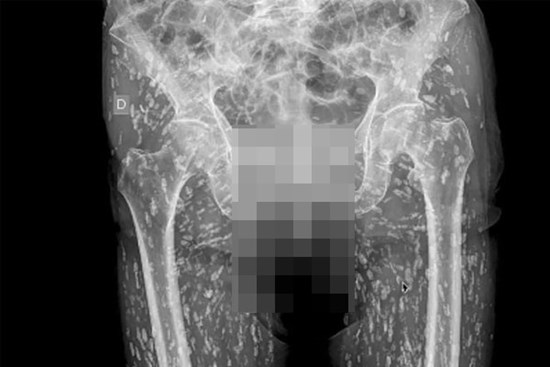

Bác sĩ Sam Ghali ở Mỹ đã phải thốt lên “Đây là kết quả chụp X-quang điên rồ nhất mà tôi từng thấy” khi khám cho một bệnh nhân nam.

Ngay sau khi chẩn đoán, bác sĩ đã tiến hành kiểm tra cộng hưởng từ và phát hiện ra rằng mô não, đầu, ngực, bụng và chân tay của anh ta đều có dấu vết của sán dây lợn.